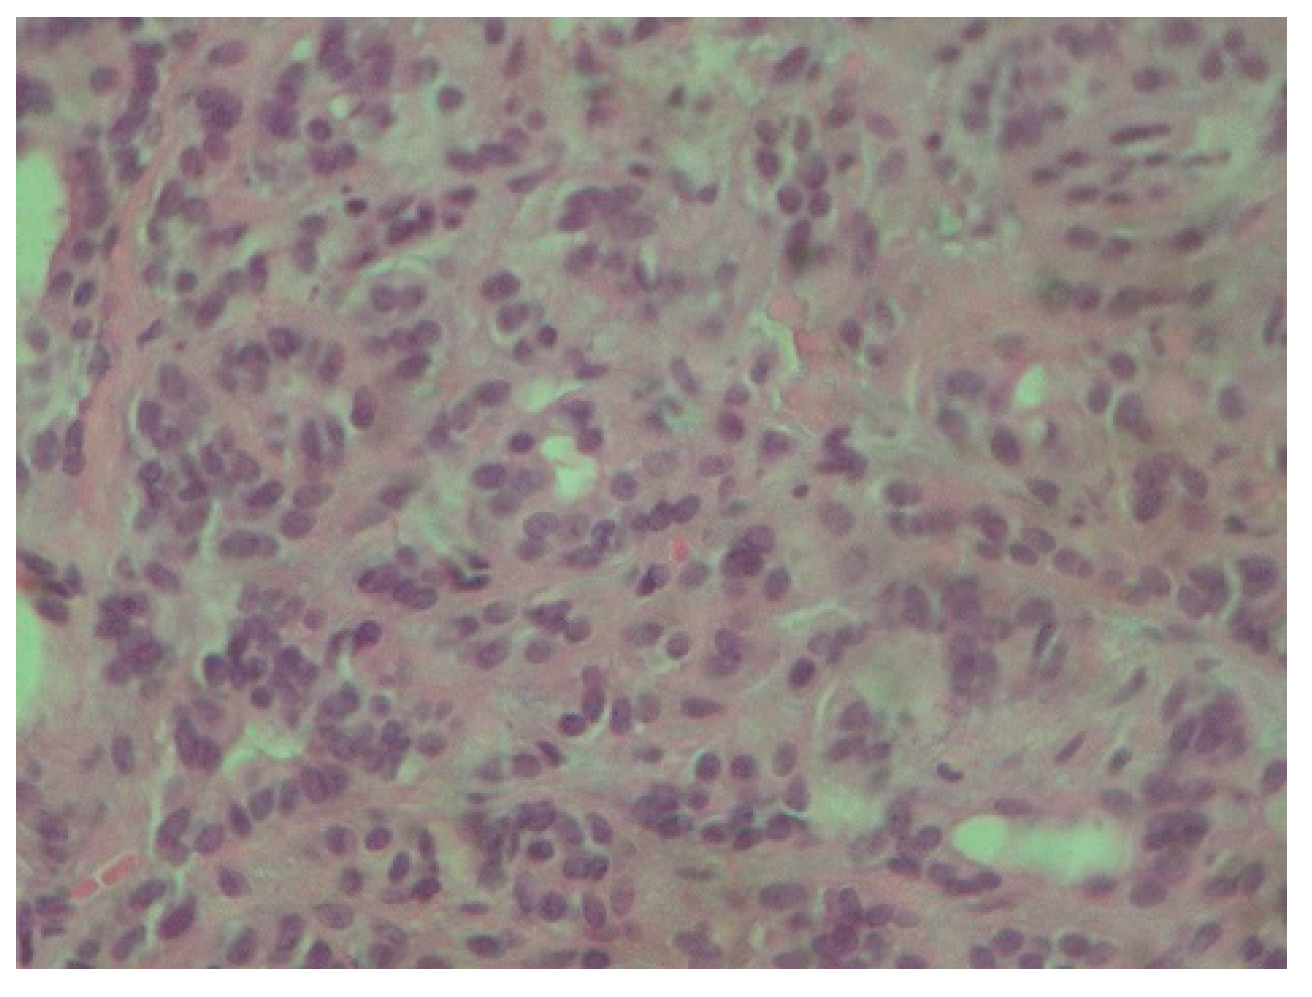

Figure 3.

Tumor cells are characterized by small, round nuclei, inconspicuous nucleoli and mild atypia. They grow in adenoid and small trabecular formations (H-E ×400).